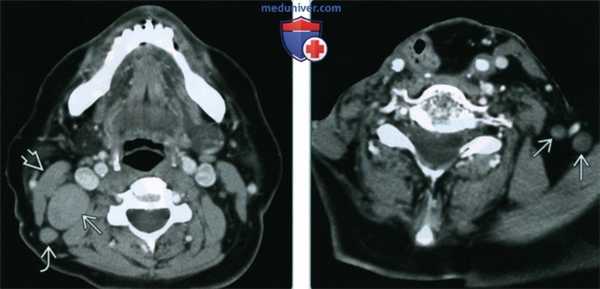

(Слева) При аксиальной КТ с КУ у женщины 83 лет с первичным ПКР передних боковых отделов языка определяется двухсторонняя лимфаденопатия второго уровня. Лимфоузлы слегка увеличены в размерах, однако выглядят округлыми и имеют неоднородную плотность. Двухсторонняя лимфаденопатия означает стадию N2c; стадия заболевания IVA.

(Справа) При аксиальной КТ с КУ у пациента с плоскоклеточным раком оральной части языка справа и метастазами в лимфоузлы уровня IIА под грудино-ключично-сосцевидной мышцей визуализируется вторично измененный лимфоузел IV уровня с неоднородной структурой. При ПЭТ и при исследовании удаленного образца подтвердилась опухоль. Лимфатических узлов III уровня не определяется. (Слева) При аксиальной КТ с КУ в задней стенке глотки на уровне подъязычной кости определяется экзофитная опухоль (ПКР) неоднородной структуры. При всех опухолях задней стенки глотки и грушевидных синусов всегда нужно оценивать заглоточные лимфоузлы, которые не поддаются пальпации.

(Справа) При аксиальной КТ с КУ у пациента с ПКР задней стенки гортаноглотки с внутренней стороны от левой внутренней сонной артерии визуализируется увеличенный заглоточный лимфоузел, пораженный опухолью, неравномерно накапливающий контраст. (Слева) При аксиальной КТ с КУ визуализируется группа округлых увеличенных лимфатических узлов третьего уровня без некротических изменений в структуре. Визуализируется также лимфоузел уровня VA, подтвержденный метастаз ПКР заперстневидной области. Первичная опухоль едва заметна на КТ, но хорошо различима на ПЭТ с ФДГ.

(Справа) При аксиальной КТ с КУ в передних отделах шеи по средней линии визуализируется округлое образование низкой плотности, накапливающее контраст по периферии в виде «ободка». Это т.н. «дельфийский» (или предгортанный) лимфоузел, который нечасто вторично поражается при ПКР Нечеткие края лимфоузла позволяют предположить эстракапсулярное распространение опухоли.